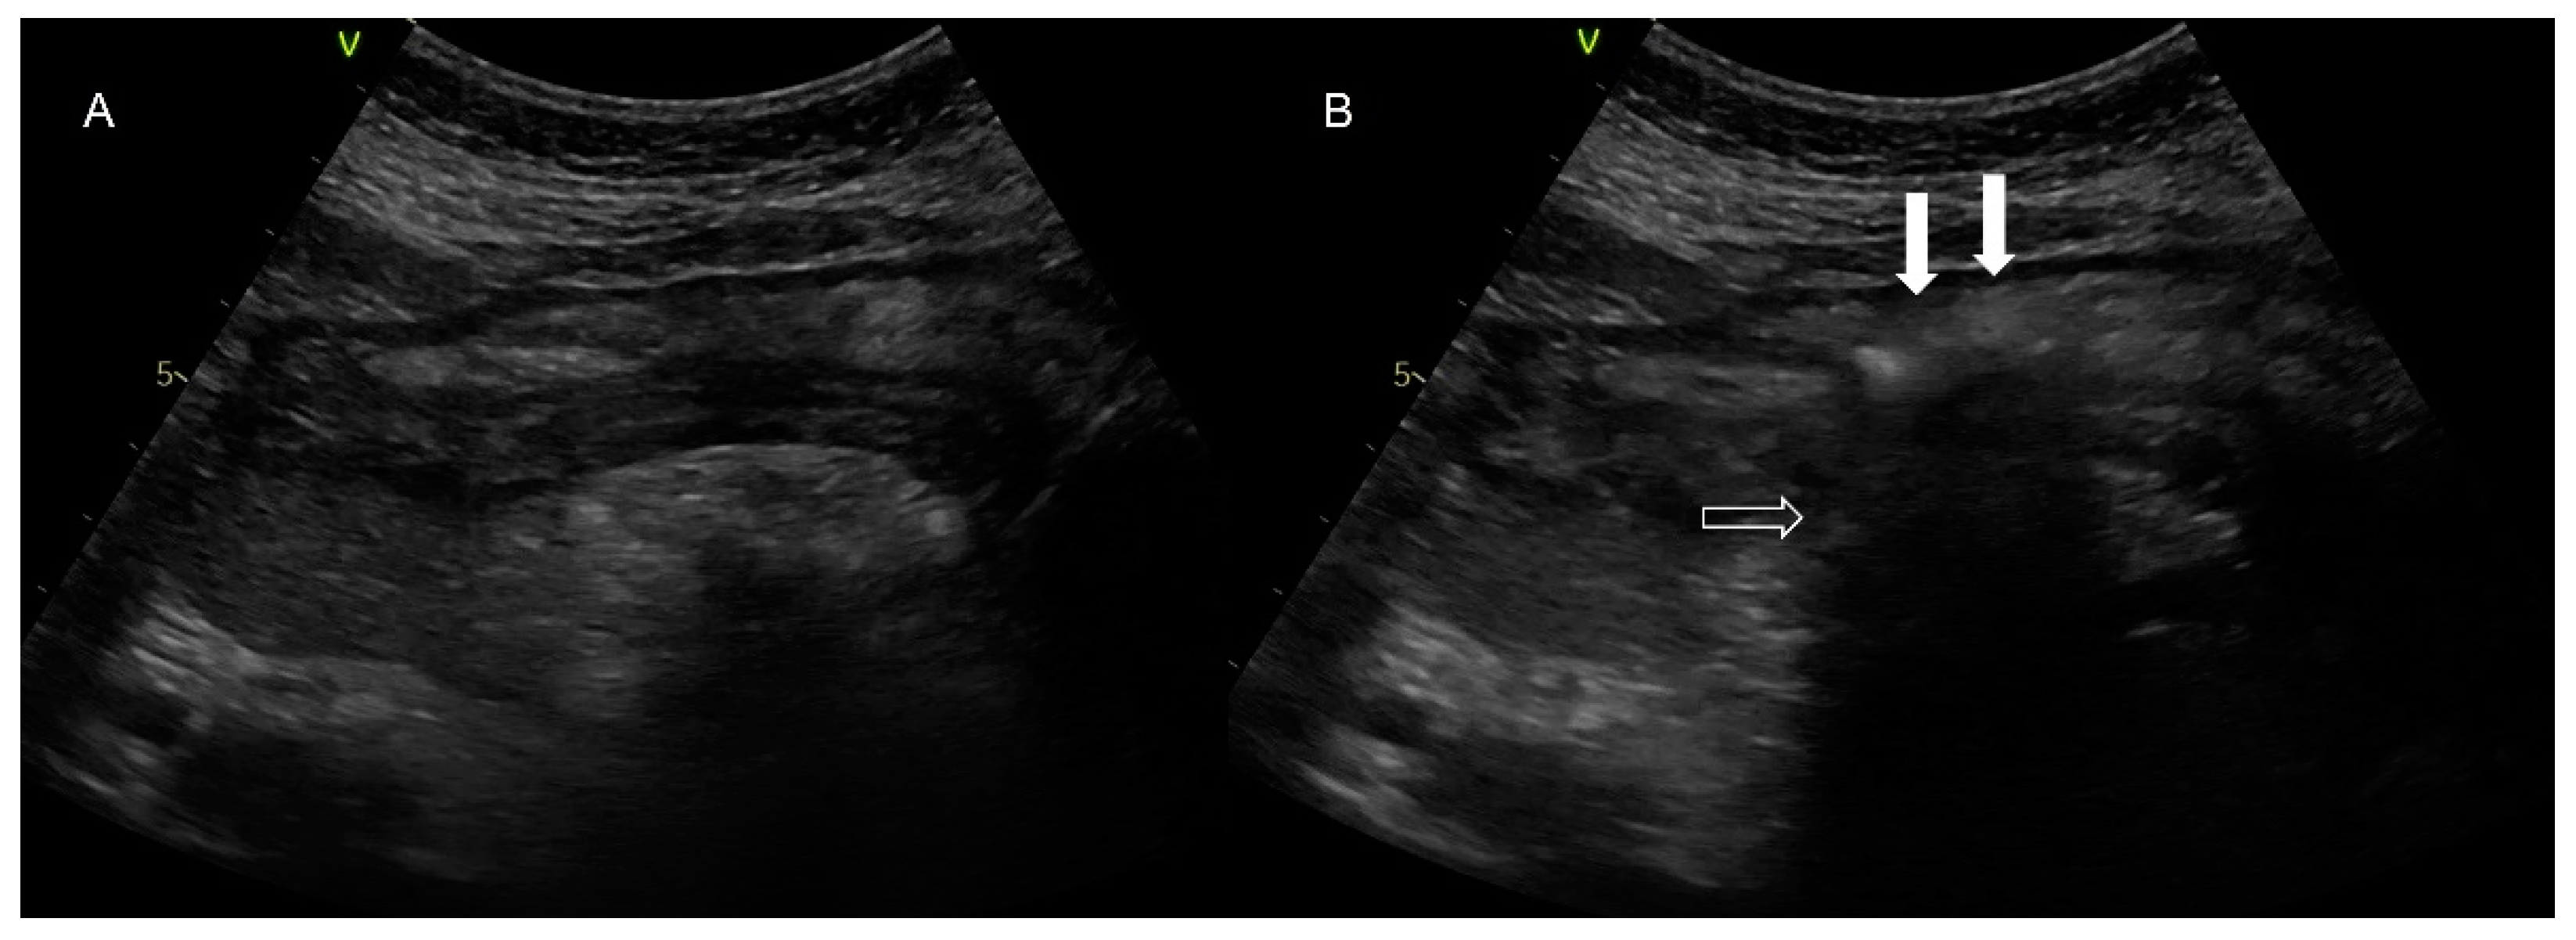

Figure 4. Abdominal ultrasonography. In picture (A), there is a presentation of the stomach at the center of the image in the longitudinal axis, while the hyperechoic structure beneath is pancreatic tissue. In picture (B), the image is obtained after instillation of a “flash” of air (white arrows) through the nasogastric tube. The pancreatic tissue is obscured (empty arrows), as an amount of air interferes between the ultrasonographic beam and the pancreas.